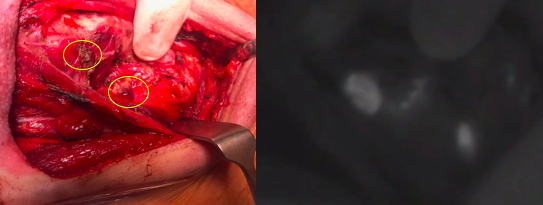

We are currently trialling autofluorescence as a novel way of addressing this… watch this space for our results….